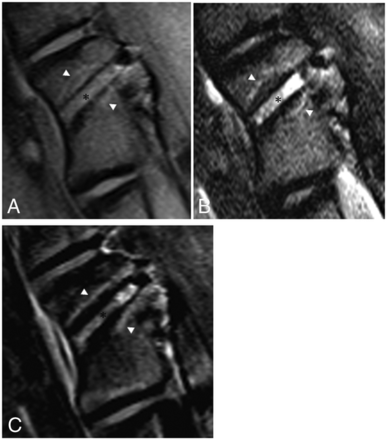

All ablation modalities produced the same subjective signal and enhancement characteristics on MR imaging (Table 5). Relative to normal marrow, the probe tracts demonstrated T1 isointense, T2 hyperintense, and enhancing tissue outlined by signal void. The ablation zones were defined by nonenhancing tissue that was slightly T1 hyperintense and T2 isointense and delineated by a thin rim of T1 and T2 hyperintensity and enhancement (Fig 4). The gross and histologic findings seen with all modalities were qualitatively similar (Table 5). Gross examination revealed discrete pale tan ablation zones. Histologically, the ablation zones were characterized by widespread marrow necrosis with areas of granulation tissue and edematous stroma. Surrounding the ablation zones were rims of hemorrhagic congestion (Fig 5).

MR imaging findings 7 days after RFA of an L2 vertebral body in a sheep model. A, T1-weighted oblique sagittal MR imaging (left, anterior; right, posterior) shows T1 hyperintense soft tissue within the probe tract (black asterisk) outlined by a signal void. The surrounding ablation zone is isointense to normal marrow and outlined by a thin hyperintense rim (white arrowheads). B, T2-weighted oblique sagittal MR imaging with fat suppression shows the hyperintense probe tract (black asterisk) and slightly hypointense ablation zone surrounded by a hyperintense rim (white arrowheads). C, T1-weighted, postcontrast subtraction images show enhancement along the probe tract (black asterisk) and the nonenhancing ablation zone surrounded by a rim of enhancement (white arrowheads).